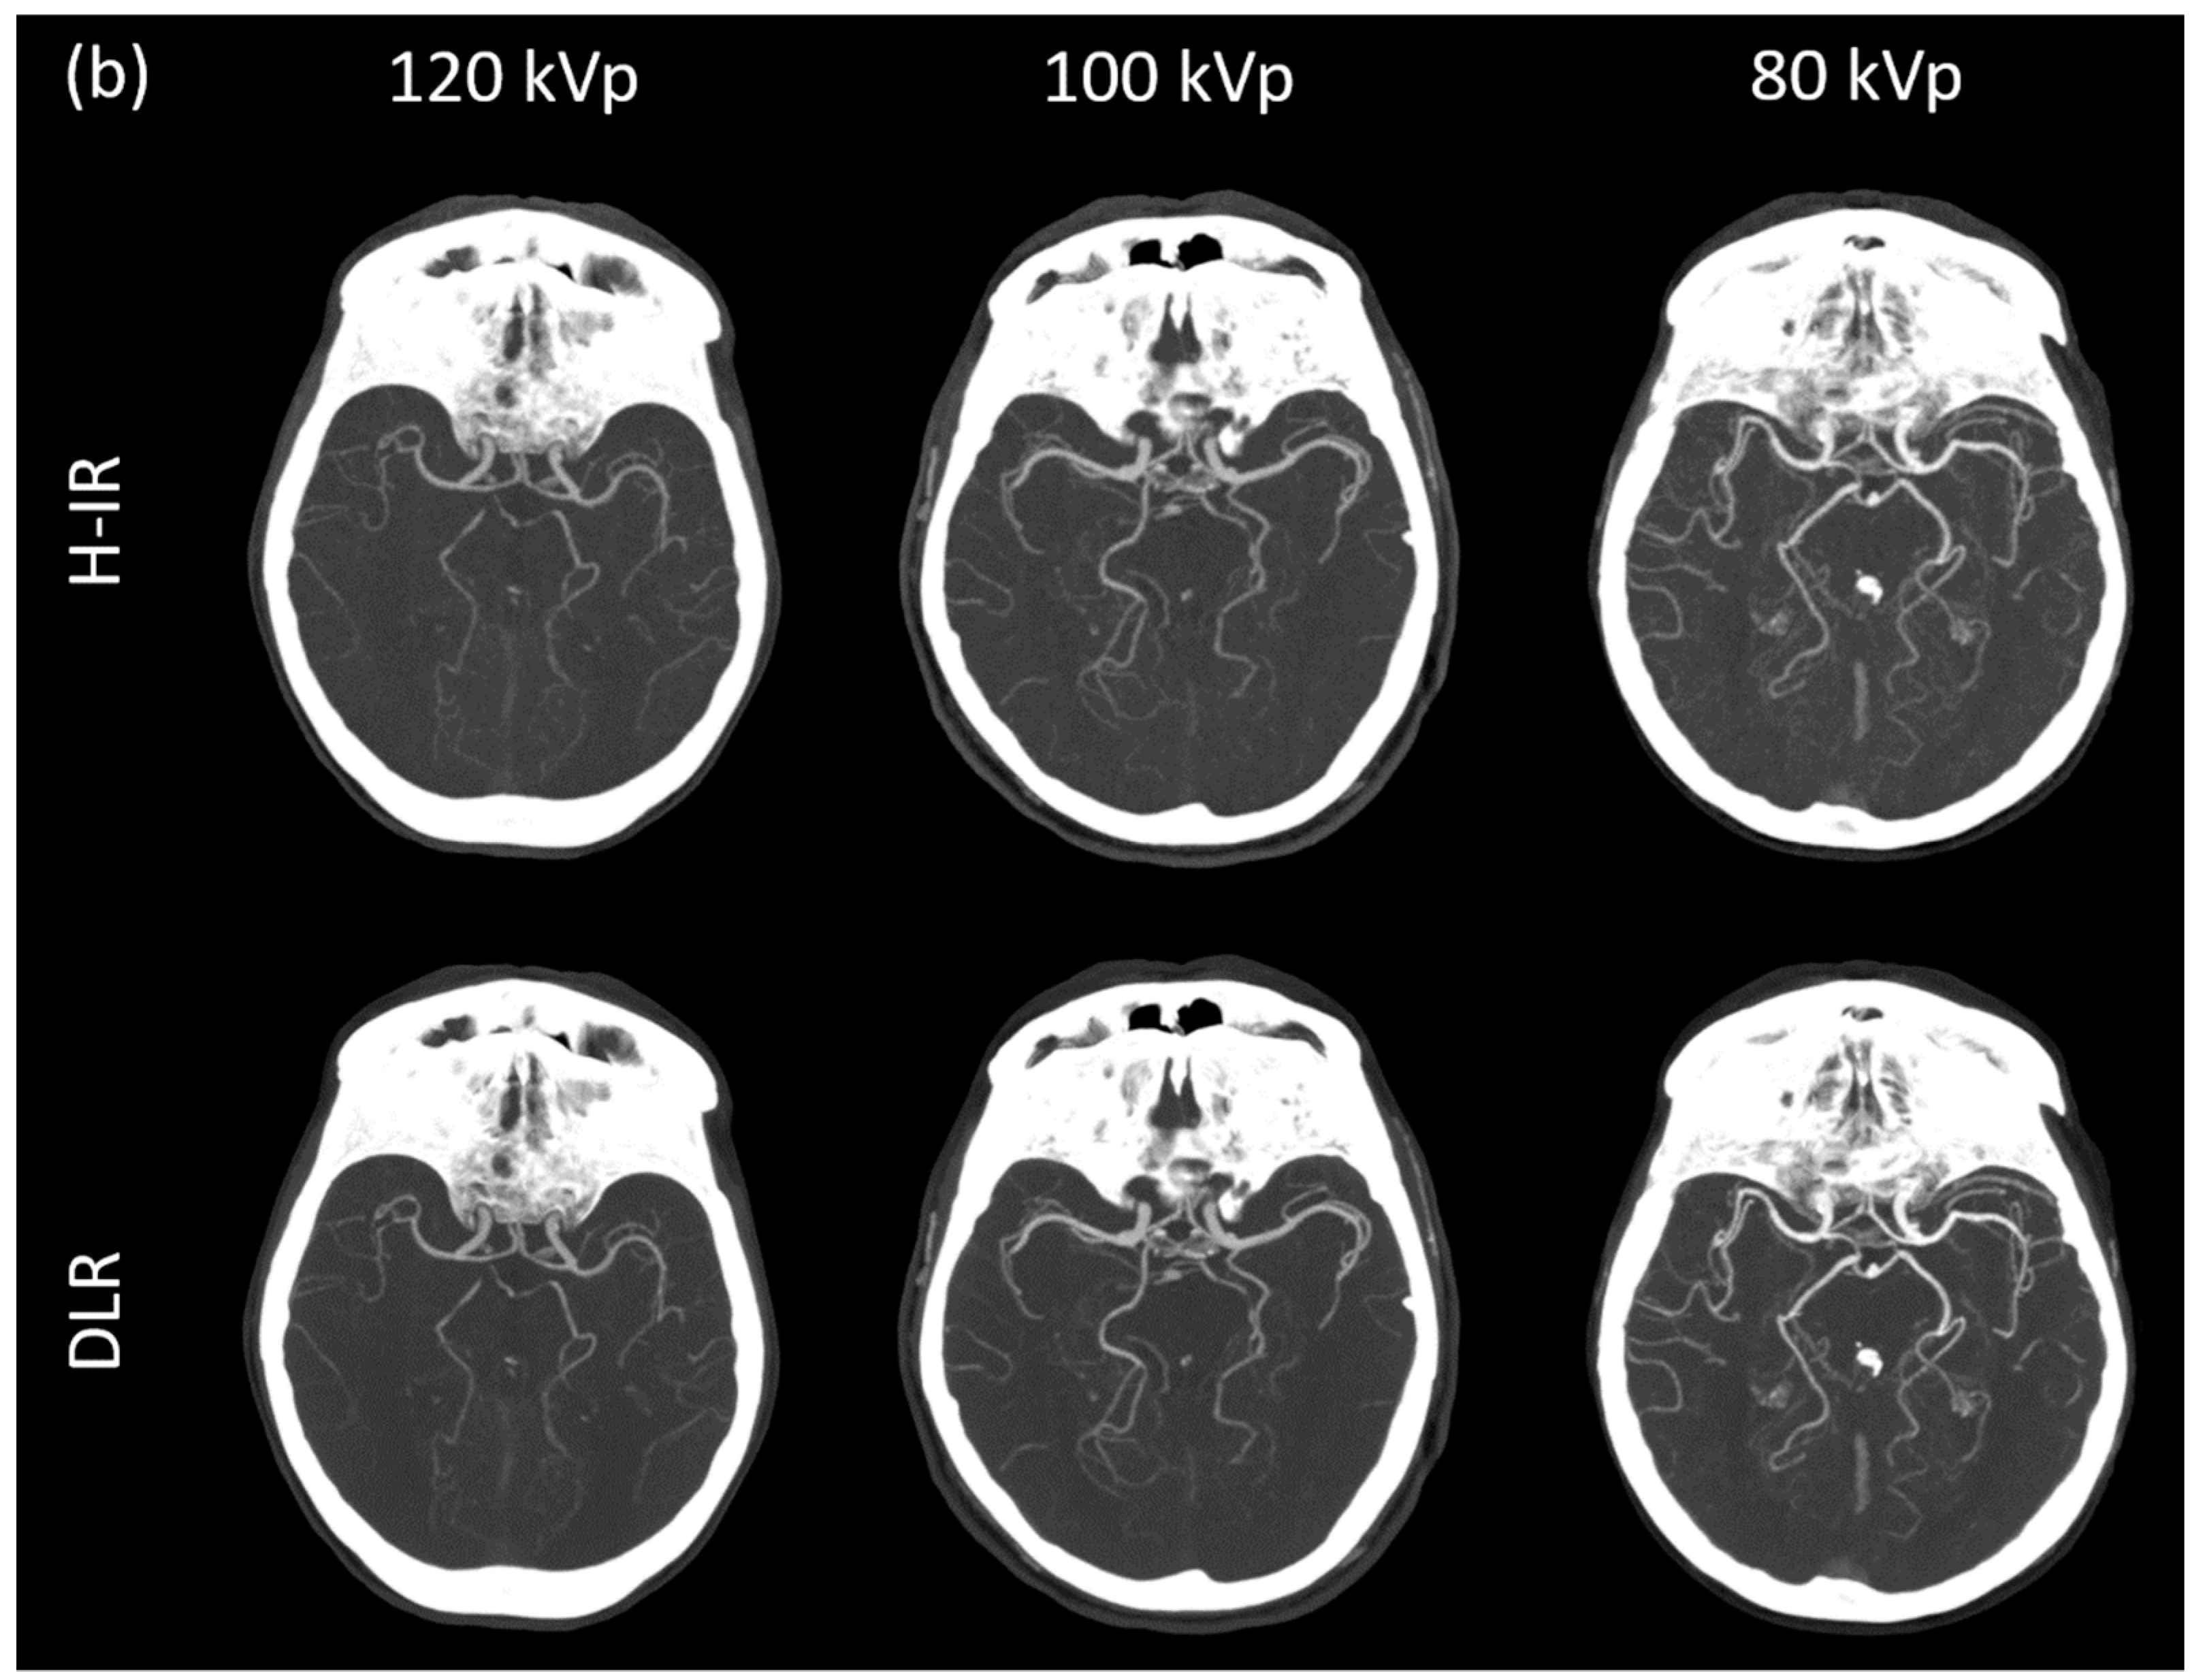

3.3.1. Image Signal Fluctuation with DLR vs. H-IR

3.3.2. Comparison of the Two Reconstruction Techniques at Constant kVp Value

3.3.3. Comparison of Low kVp plus DLR vs. Standard kVp plus DLR

3.3.4. Comparison of Low kVp plus DLR vs. Standard kVp plus H-IR